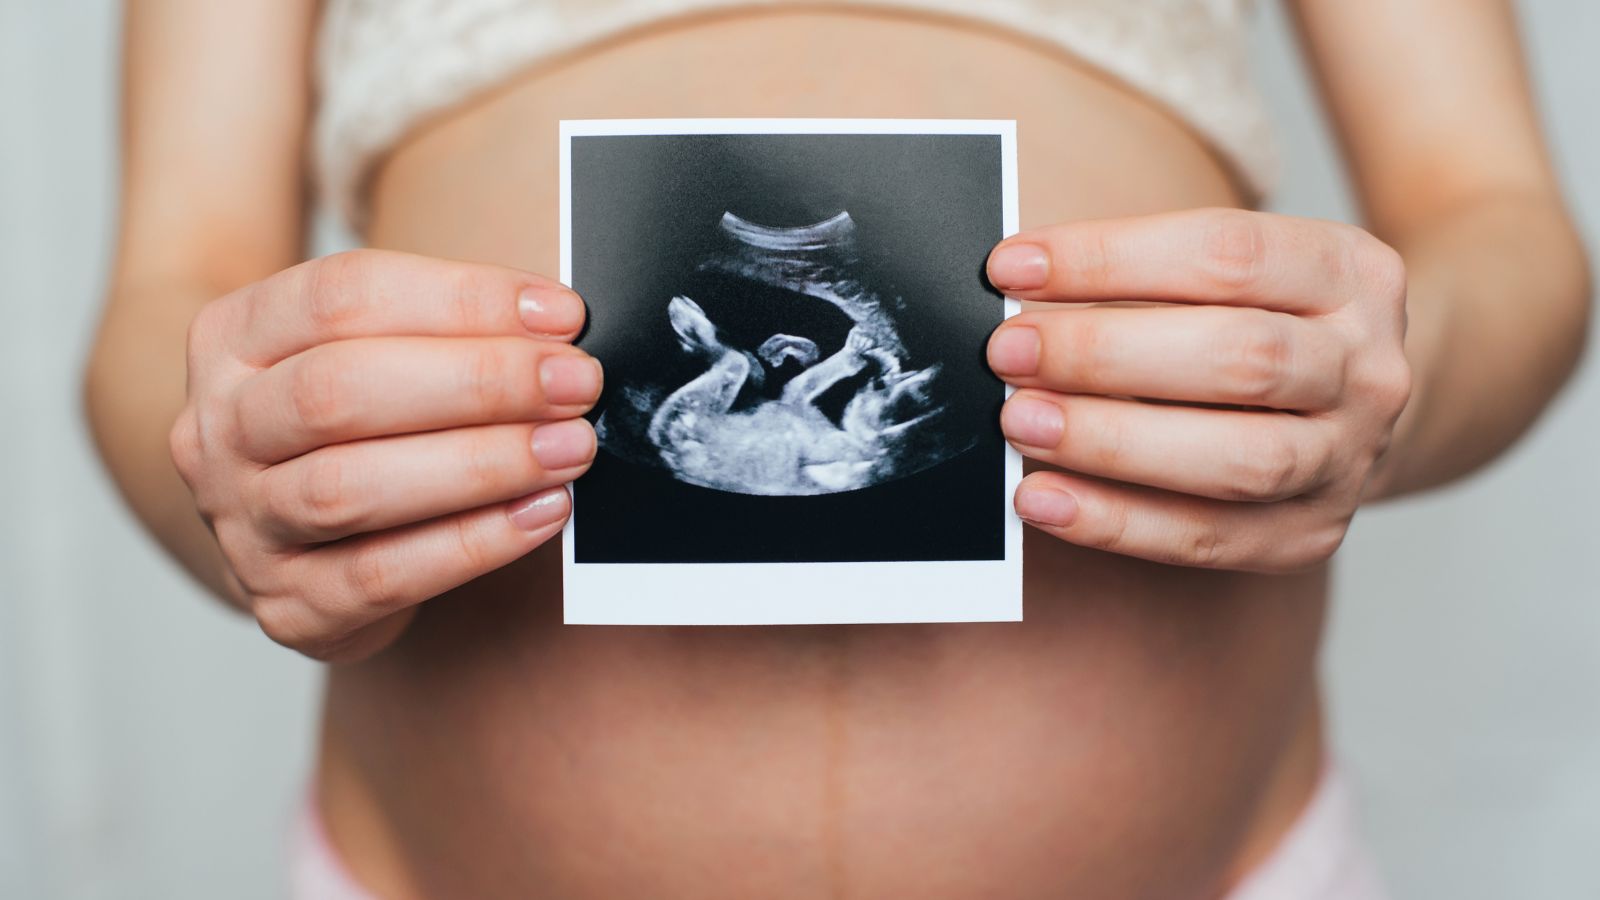

Siêu âm thai định kỳ

Siêu âm là phương pháp tốt nhất giúp phát hiện sớm tình trạng giãn quai ruột ở thai nhi. Thông qua siêu âm, bác sĩ có thể xác định mức độ giãn quai ruột và theo dõi sự phát triển của hệ tiêu hóa của thai nhi qua từng giai đoạn. Mẹ bầu nên thực hiện các lần siêu âm thai định kỳ theo chỉ dẫn của bác sĩ để kịp thời phát hiện bất kỳ vấn đề nào.